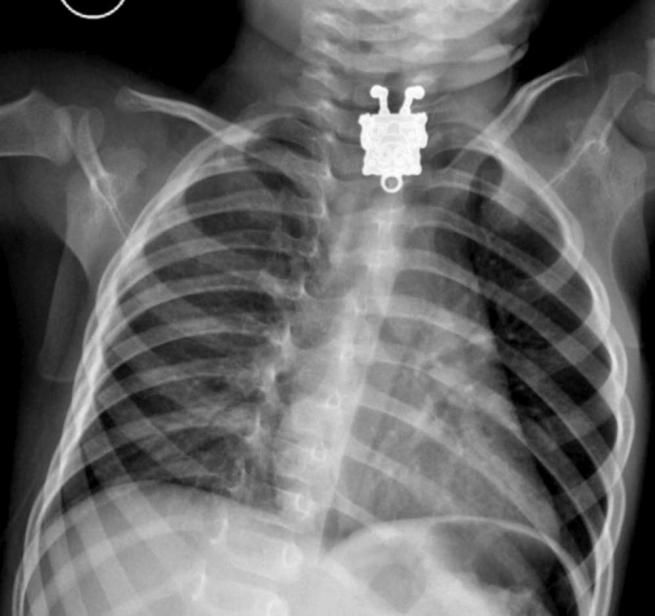

A 16 mesi ingoia il pupazzo di SpongeBob, la radiografia mostra la sagoma del giocattolo